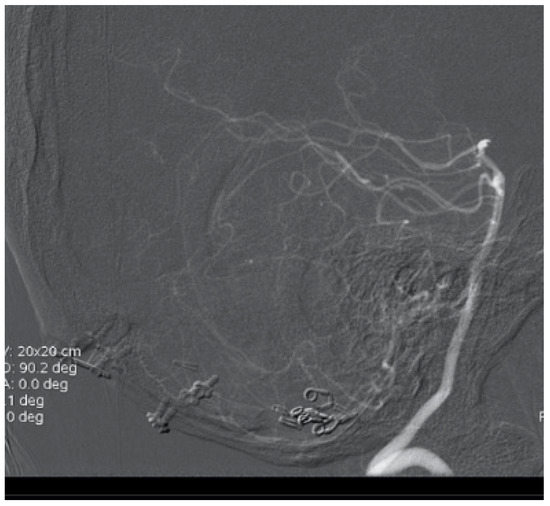

A 50-year-old man presented with a headache. Magnetic resonance imaging (MR) and angiography showed cerebellar AVM and two aneurysms on the right side of the PICA (Figure 6 and Figure 7). The patient underwent an operation, and AVM was successfully resected with both aneurysms clipped. The control angiogram showed good result of the treatment (Figure 8), the postoperative course was without complication, and the patient was discharged.

Figure 8. Postoperative control with radical AVM resection and successful clipping of PICA aneurysm.